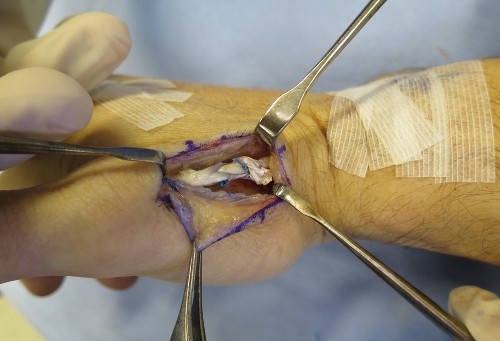

2. EI to EPL tendon transfer.

- There are 2 tendons that extend the Index finger ( EI & EDC tendons)

- The EI tendon is available for transfer because the EDC tendon to the index finger can still provide normal index finger extension on its own

- The Extensor Indicis (EI) tendon (used to extend the index finger) is redirected to take over the function of the EPL.

- Surgery is usually performed as a day procedure.